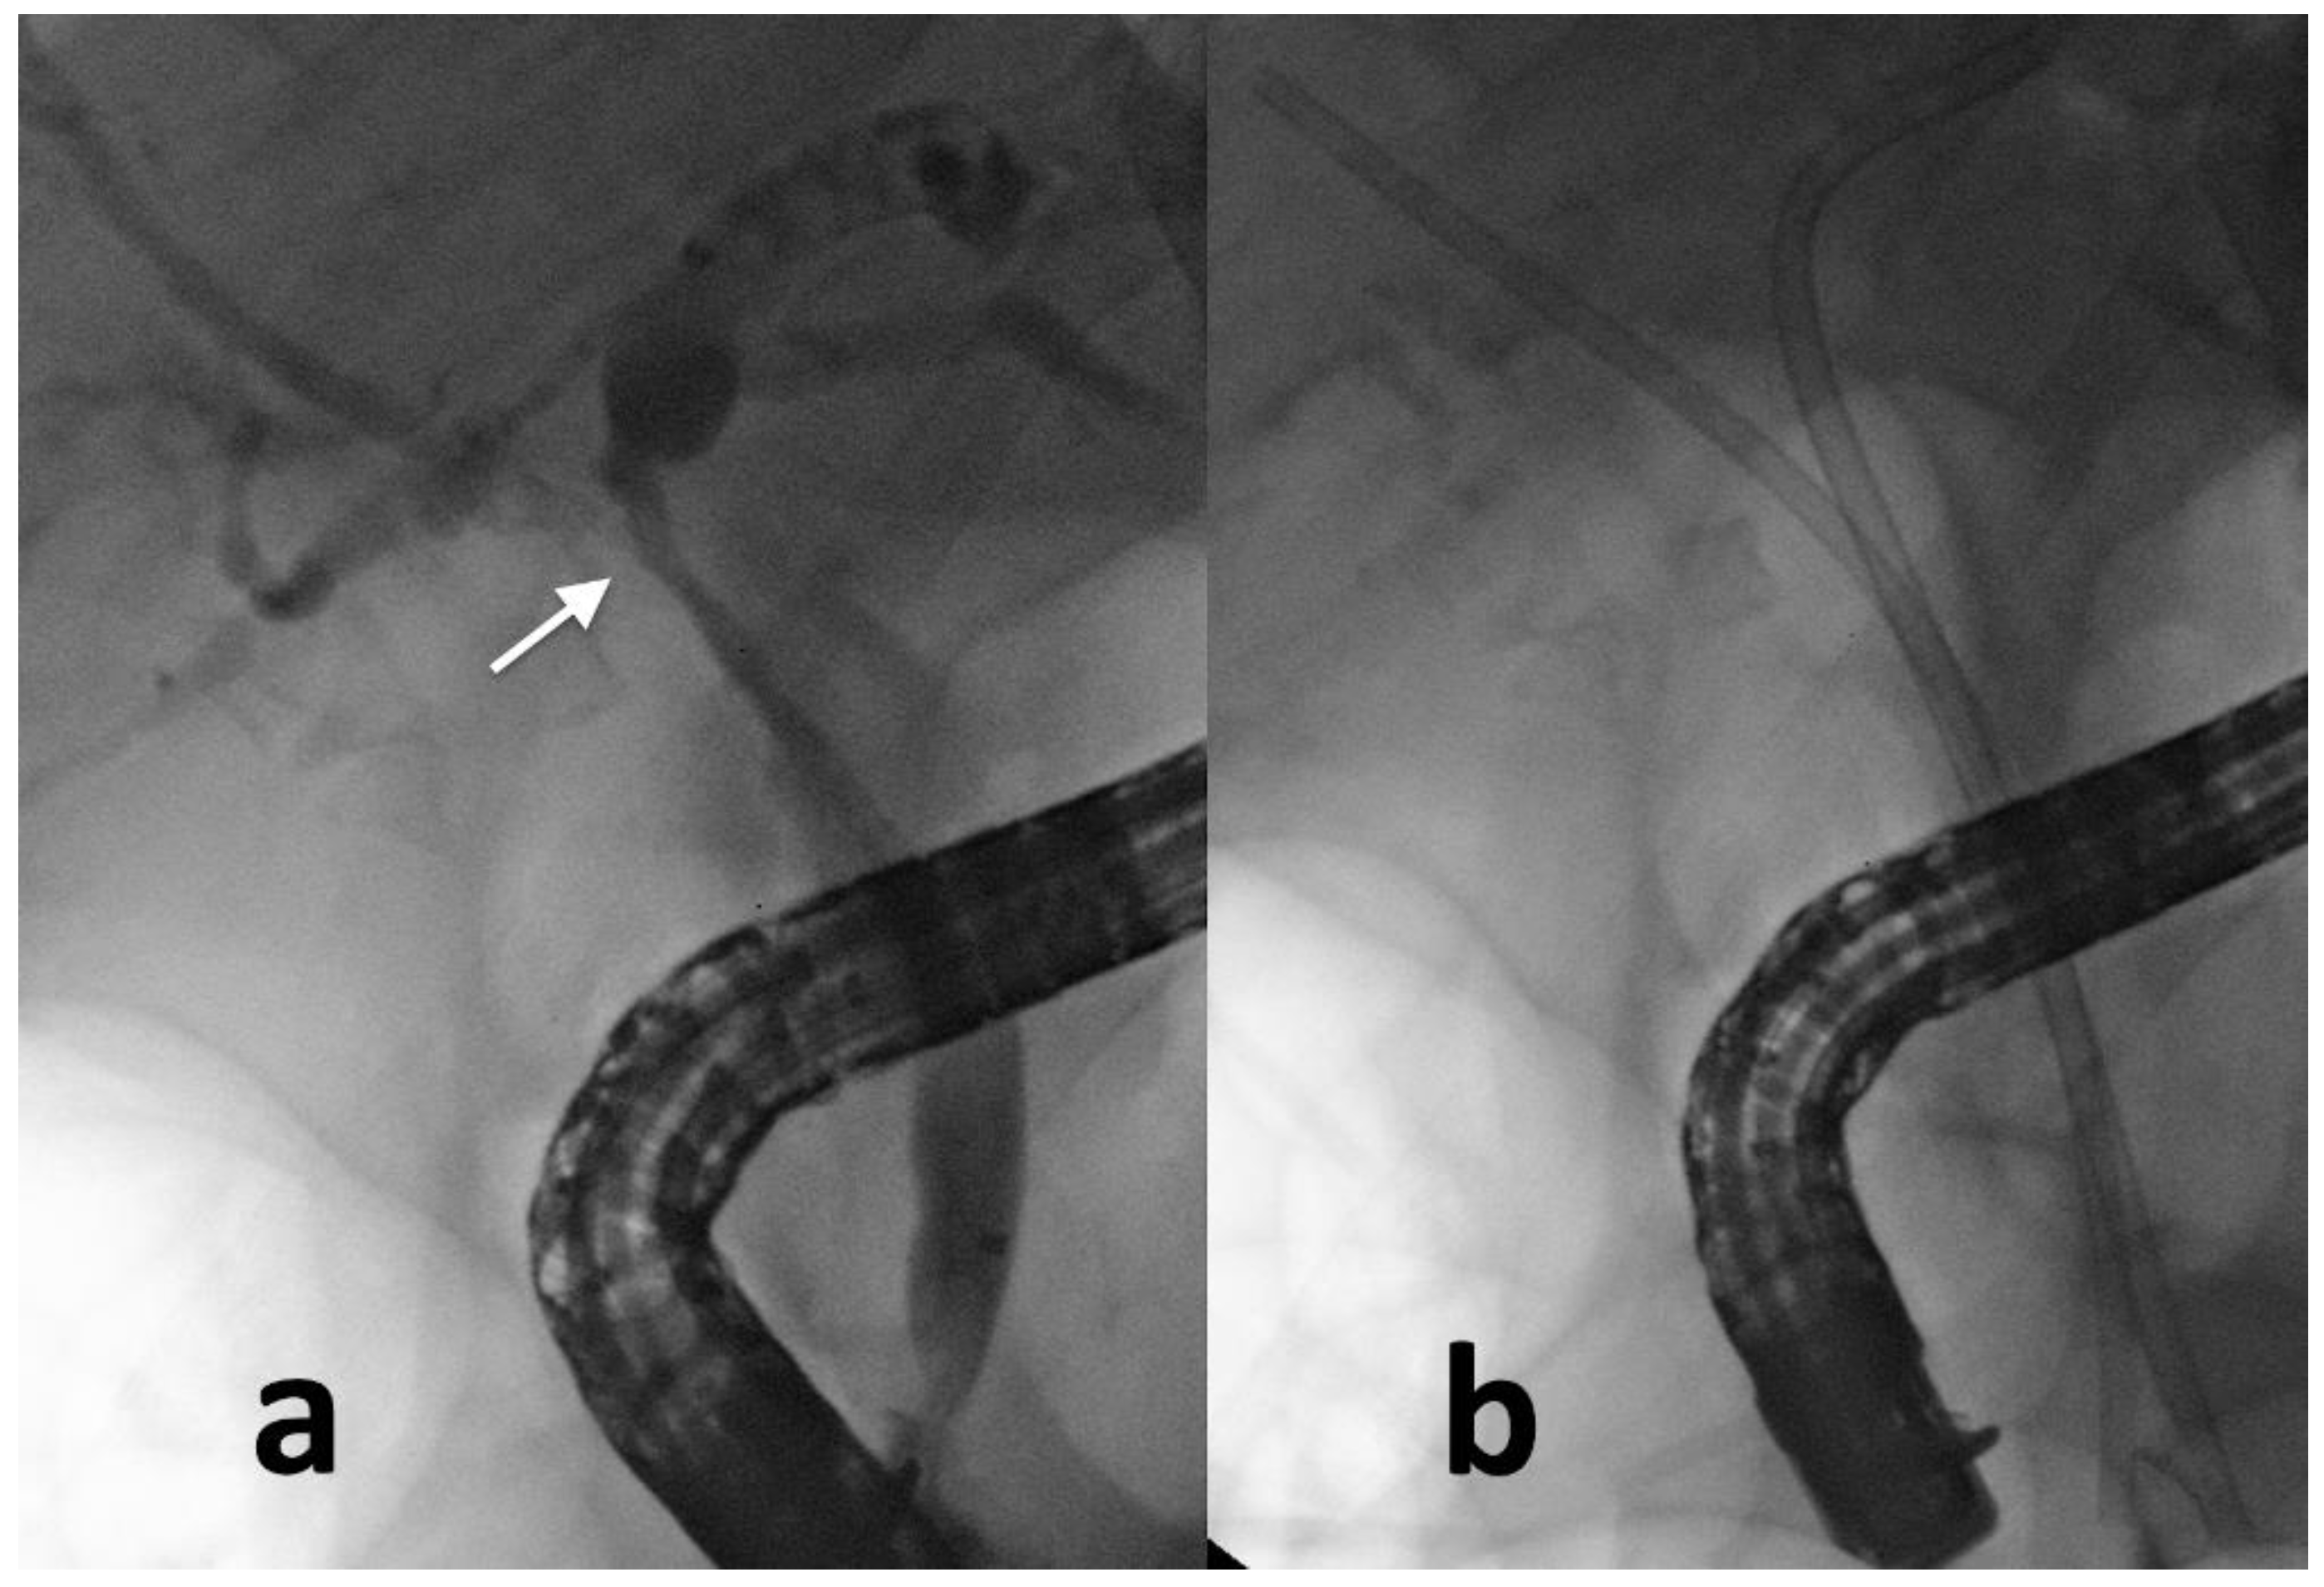

2.1. ERCP-Guided Biliary Drainage

- Kitamura, K.; Yamamiya, A.; Ishii, Y.; Mitsui, Y.; Nomoto, T.; Yoshida, H. Side-by-side partially covered self-expandable metal stent placement for malignant hilar biliary obstruction. Endosc. Int. Open 2017, 5, E1211–E1217. [Google Scholar] [CrossRef] [PubMed][Green Version]

- Boškoski, I.; Schepis, T.; Tringali, A.; Familiari, P.; Bove, V.; Attili, F.; Landi, R.; Perri, V.; Costamagna, G. Personalized Endoscopy in Complex Malignant Hilar Biliary Strictures. J. Pers. Med. 2021, 11, 78. [Google Scholar] [CrossRef]